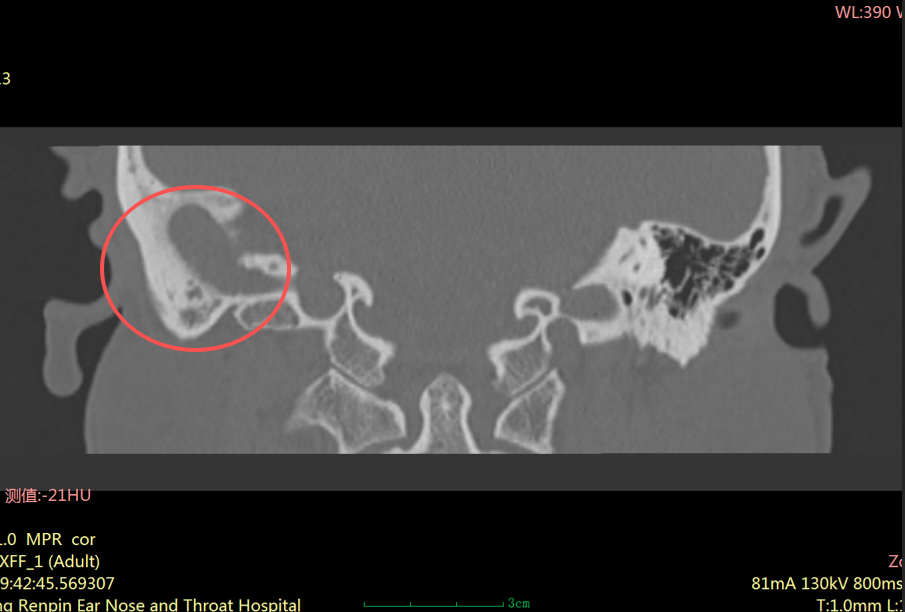

“患者右耳中耳腔已形成胆脂瘤,它像一颗不断侵蚀听骨的‘定时炸弹’,若再拖延,可能引发面瘫、颅内感染等严重并发症。”耳科主任张朝梅指着CT影像解释道。

虽然它不是肿瘤,但危害却不容小觑。它会像“寄生虫”一样,不断破坏周围的骨质,可能侵犯中耳的听小骨、面神经管、半规管等重要结构,进而导致听力下降、耳鸣、面瘫,严重时甚至可能引发颅内感染,危及生命。

明确诊断后,张主任针对其病情进行了全面评估——患者的胆脂瘤已经对中耳结构造成了一定破坏,保守治疗效果不佳,为彻底清除病灶,同时尽可能恢复听力,张主任制定了个性化的手术方案: